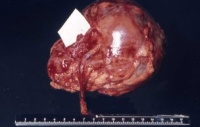

Auf der Schnittfläche ist der Tumor von gelbbrauner bis grauer Farbe mit einzelnen Einblutungen. Zystische Anteile und Nekrosen kommen vor sowie oberflächlich glatte, knotenförmige Strukturen, ähnlich einem Rhabdomyosarkom (Abbildung 1a-d).

Literatur:Richmond, H. et al: "Neonatal Renal Tumors", J Pediatr Surg, 5, 413-417, 1970. Der Tumor ist oberflächlich glatt, z.T. bucklig, von weißgrauer Farbe (s. Abbildung 1d). Ein von der Makroskopie her vergleichbares Bild wie bei dem Wilmstumor des 8 Monate alten Mädchens. Histologisch unterscheidet sich das Nephrom vom Wilmstumor, der zumeist ältere Kinder betrifft. Es finden sich dicht verflochtene Bündel von Spindelzellen mit elongierten Kernen, die das renale und perineale Gewebe infiltrieren, Einschlüsse von Glomeruli und Tubuli in das Tumorgewebe sind häufig. In wie weit das mesoblastische Nephrom zur Gruppe der Wilmstumoren gehört, ist fraglich. Die Prognose des mesoblastischen Nephroms ist gut. Metastasen sind selten